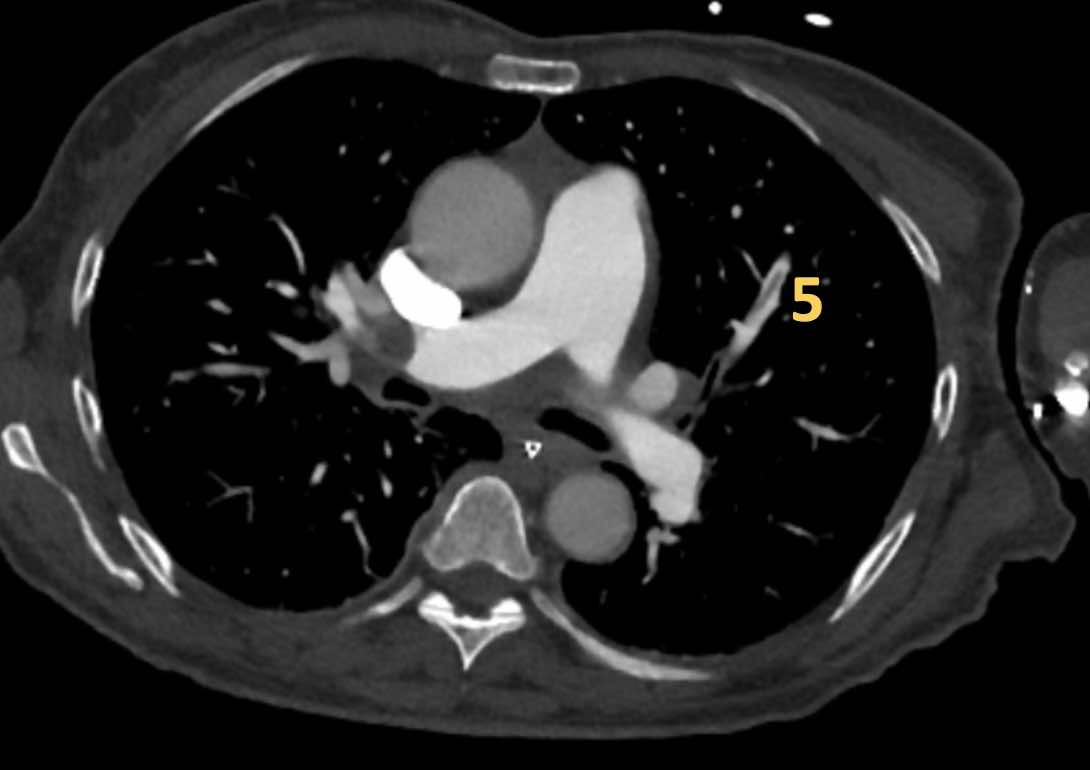

Có huyết khối phân thùy tắc nghẽn cấp tính trên nền mạn tính ở phân thùy trước của thùy trên phổi trái

(mũi tên đen).

Tắc nghẽn phân thùy có sẵn ở các nhánh đáy với hẹp đột ngột của các mạch máu ngoại vi (mũi tên xanh).

Đây là các hình ảnh của bệnh nhân nam 53 tuổi

mắc tăng áp động mạch phổi.